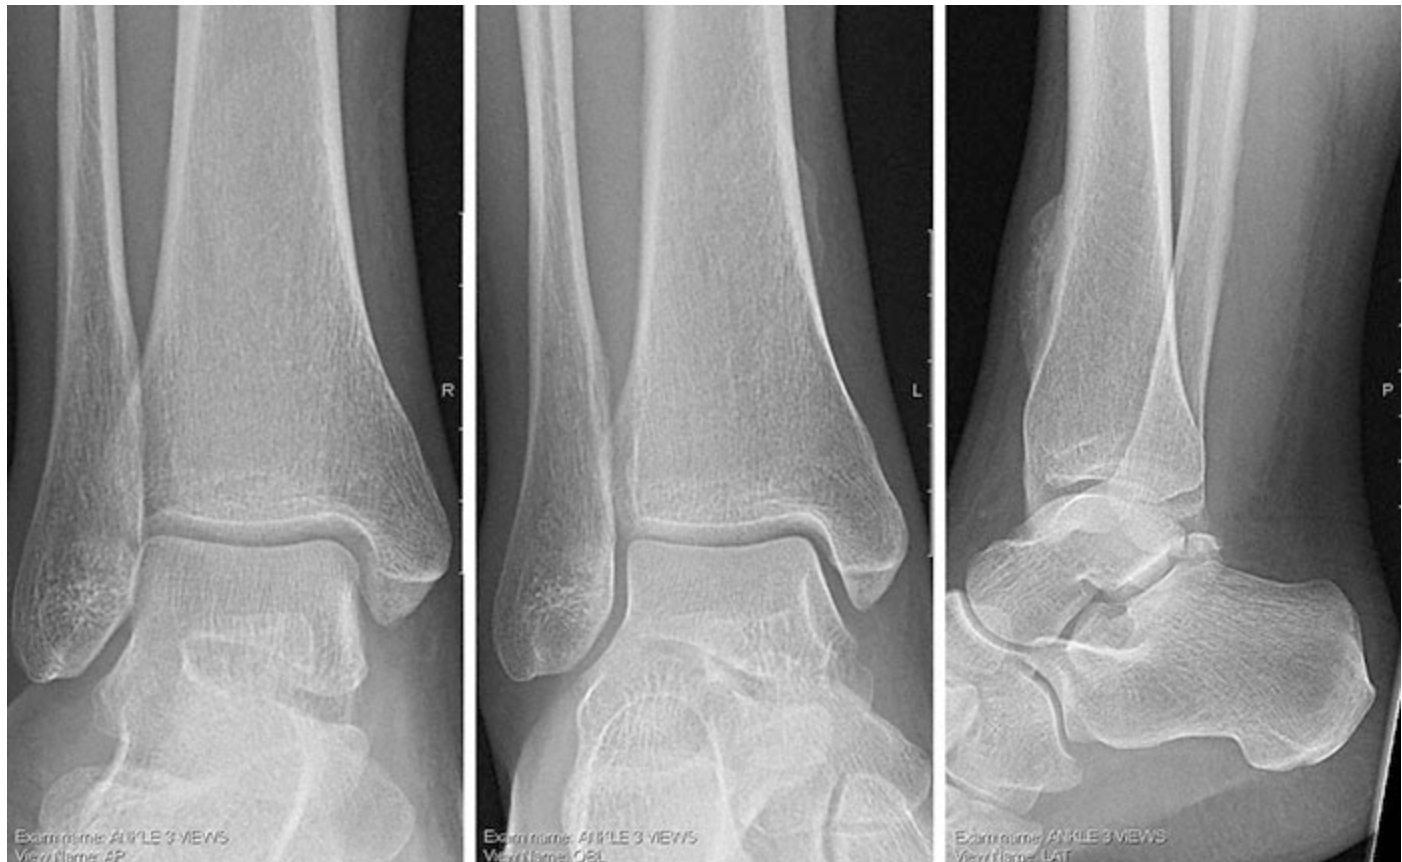

A 22-year-old woman comes to the office because of a 6-week history of mild pain and swelling in the front of her right ankle. She says her symptoms began after she awkwardly stepped off a curb. There is no personal or family history of serious illness. Her only medication is ibuprofen as needed for pain. She does not smoke cigarettes or drink alcohol. Vital signs are within normal limits. Examination shows a 1 -cm abrasion and mild ecchymosis over the anterolateral aspect of the right ankle. There is warmth and swelling at the right anterior ankle joint; passive dorsiflexion produces pain. Anterior drawer test is negative bilaterally. Muscle strength is 5/5 on inversion, eversion, dorsiflexion, and plantar flexion of the right ankle. Dorsalis pedis pulses are 2+ bilaterally. Sensation to light touch is intact over the lower extremities. X-rays of the right ankle are shown. Which of the following is the most appropriate next step in diagnosis?